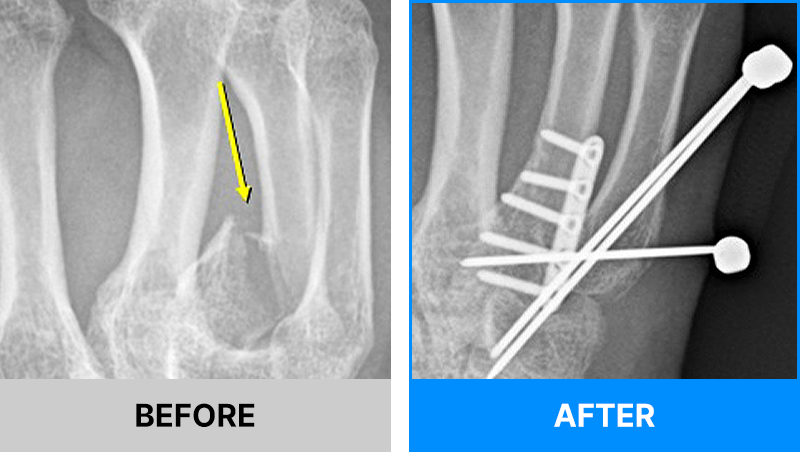

왜 당일 입퇴원 수술일까요?

오래 입원할 필요가 없기 때문입니다.

서울거탑정형외과에서는 전신마취, 척추마취가 아닌

국소부분마취(신경차단) 및 수면 마취를 통해 수술을 시행합니다.

수술 가능 여부 확인은 대표원장과의 진료가 필요합니다.